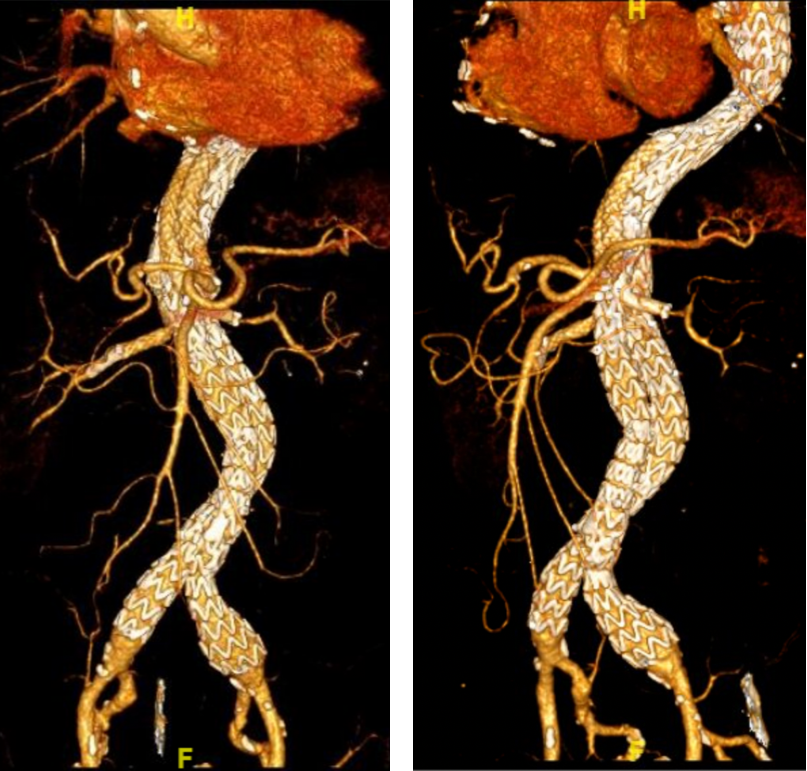

术后1年复查:各分支通畅,无内漏

随访(3-12月):20支重建分支全部通畅。